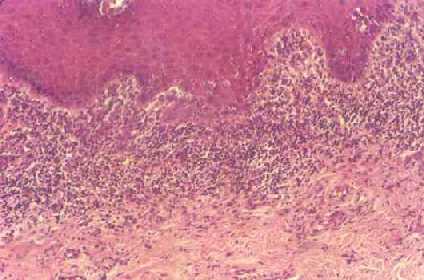

El liquen plano es una enfermedad poco común que causa erupción o lesión inflamatoria y picazón recurrentes en la piel o en la boca. No se conoce la causa exacta de esta enfermedad, pero es probable que esté relacionada con una reacción alérgica o inmune.

Un aspecto característico de la lesión cutánea asociado con antecedentes de recurrencia de las lesiones puede ser un indicador de la presencia de liquen plano. El médico o el odontólogo pueden diagnosticar el liquen plano oral con base en el aspecto característico de las lesiones orales. El diagnóstico se confirma por medio de una biopsia de la lesión cutánea o una biopsia de la lesión oral.